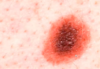

On which surfaces does psoriasis tend to present?

Extensor with silver plaques

Recall the pathophysiology of psoriasis

Normal keratinocyte turnover time = 56 days

Psoriasis keratinocyte turnover time = 7 days

- Rapid turnover → epidermis thicker

- layer of parakeratosis at the top

- Stratum granulosum disappears as not enough time to form it; and dilated vessels form

- Munro’s microabscesses form, made up from recruitment of neutrophils

Which skin pathology appears as “silvery plaques”?

Psoriasis